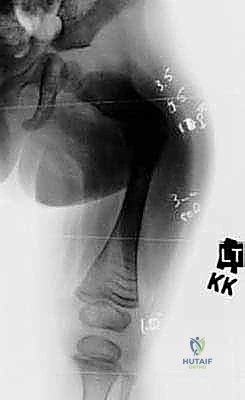

الخطوة الأولى: التخطيط الجراحي الدقيق (Pre-operative Planning)

قبل العملية، يقوم الدكتور هطيف بإجراء دراسة شاملة لصور الأشعة السينية (X-rays) المأخوذة بدقة، لحساب زوايا التقوس بدقة متناهية، وتحديد نقاط بضع العظم (أماكن القص)، واختيار الحجم والطول المناسبين للمسمار التلسكوبي.

الخطوة الرابعة: إدخال المسمار التلسكوبي

بعد تقويم العظم وجعله مستقيماً كحبات المسبحة على خيط، يتم إدخال السلك الدليلي (Guide Wire). ثم يتم إدخال الجزء الخارجي (الأنثوي) من المسمار التلسكوبي وتثبيته في الجزء العلوي من العظم (Epiphysis).

بعد ذلك، يتم إدخال الجزء الداخلي (الذكري) من المسمار عبر الجزء السفلي من العظم وتثبيته في المشاشة السفلية. هذا التصميم العبقري يضمن حماية العظم بالكامل من الداخل.

- يتم إجراء أشعة سينية للتأكد من بدء تكوّن الدشبذ العظمي (Callus) حول مناطق القص.